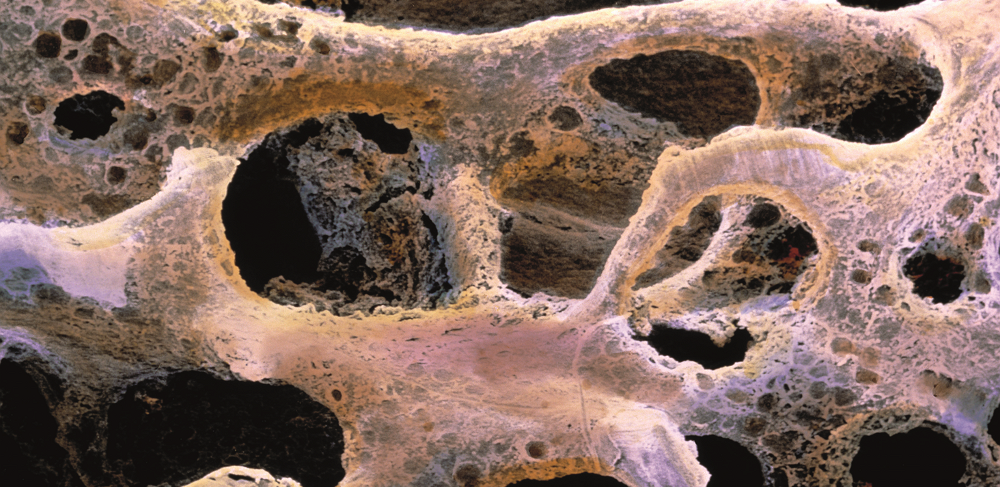

골다공증 원인은 뼈가 약해지면서 뼈에 구멍이 많이 나는 질환을 말합니다.

뼈의 골질량 감소, 구조적인 이상이 생기며 뼈가 약해져서 부러지기 쉬운 상태가 되는 질병이 골다공증입니다.